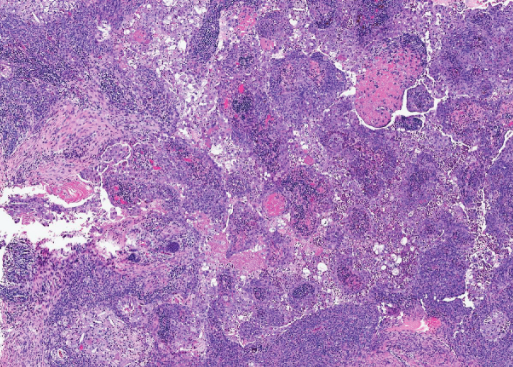

Χρώση αιματοξυλίνης-ηωσίνης. Εκτεταμένη σμηγματώδης διαφοροποίηση των νεοπλασματικών κυττάρων σε όλη την έκταση της βλάβης με ευδιάκριτα σμηγματώδη οζίδια και εστίες απόπτωσης και νέκρωσης εντός των νεοπλασματικών νησίδων. Τα νεοπλασματικά κύτταρα παρουσιάζουν έντονη μιτωτική δραστηριότητα (Ευγενική παραχώρηση Dr. V. Penopoulos)